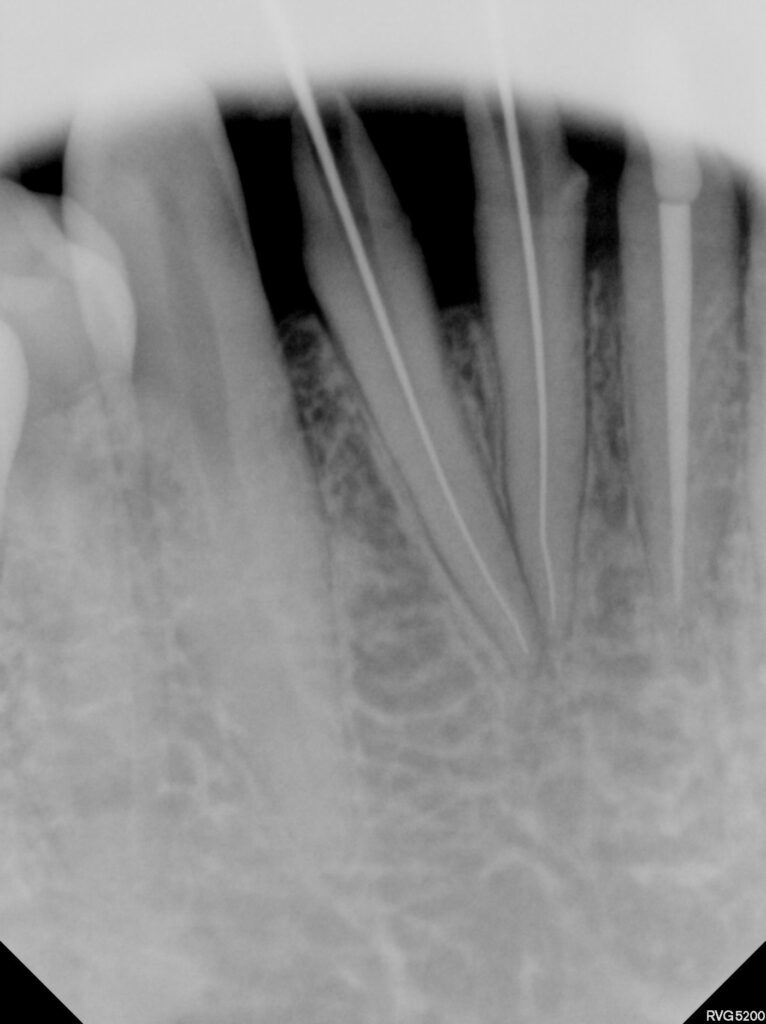

4개의 치아 중 문제가 있는 치아를 감별하기 위해

러버댐으로 치아를 격리하고 ICE / Hot test 시행하여

감별진단하였습니다.

처음 내원 시 마취도 잘 되지 않을 정도의

심한 치수염 상태였으나 신경치료를 한번

진행하고 난 후에는 통상적인 과정으로

진행할 수 있었습니다.

모든 크라운을 제거해보니 이전 치과에서

너무 치아삭제를 많이 해서 치수염이 발생했던 것으로

판단되었습니다.